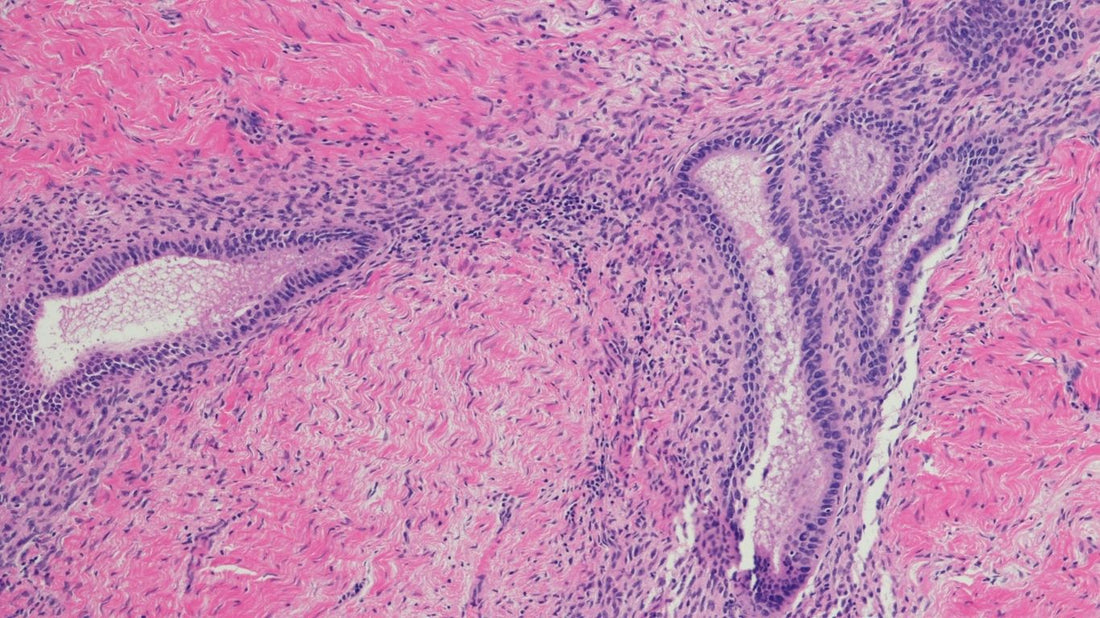

Qu’est ce que l’endométriose ? L’endométriose est une maladie inflammatoire chronique qui touche environ 1 femme sur 10 en âge de procréer. Elle se caractérise par la présence anormale de tissu endométrial (endomètre) en dehors de l’utérus (ovaires, trompes, vessie, intestin..) Sous l’influence des hormones, ces tissus réagissent comme la muqueuse utérine normale, ils s’épaississent, saignent mais ne peuvent pas s’évacuer ce qui entraîne une inflammation chronique, des douleurs, des adhérences et parfois une infertilité. Quels sont les signes de l'endométriose ? Les symptômes les plus fréquents sont des règles très douloureuses, des douleurs pelviennes chroniques( même en dehors des règles), des douleurs lors des rapports sexuels, des troubles digestifs ou urinaires, une fatigue chronique, des difficultés à concevoir un enfant. Quelles sont les causes de l’endométriose ? La cause exacte n’est pas encore connue mais plusieurs facteurs semblent impliqués : génétique immunité facteurs environnementaux Il n’existe pas à ce jour de traitement curatif définitif mais plusieurs approches permettent de soulager les symptômes et préserver la fertilité comme : les traitements hormonaux la chirurgie dans les cas les plus sévères l’approche complémentaires et naturelles elle va permettre la réduction de l’inflammation notamment via le zinc et de la vitamine D la gestion de stress grâce au magnésium